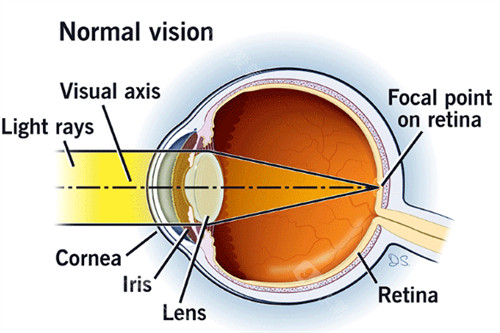

科室引进了一系列较高的眼科检查和治疗设备,如光学相干断层扫描仪(OCT)、眼底荧光血管造影仪等,这些设备能够为医生提供比较准的诊断依据,帮助医生更精密地了解患者的病情。

在治疗方面,科室拥有较高的激光治疗设备,可用于治疗多种眼科疾病,如青光眼、糖尿病视网膜病变等。